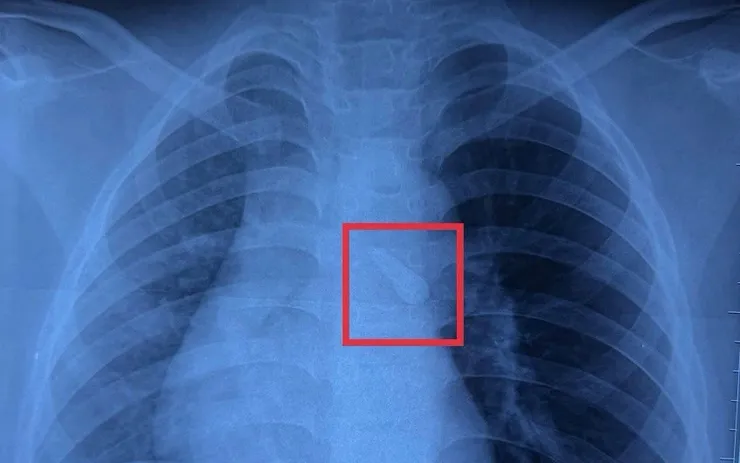

Kết quả chụp X-quang ghi nhận dị vật cản quang trong khí quản. Khai thác bệnh sử cho thấy trẻ bị mất răng số 21 sau tai nạn, các bác sĩ nghi ngờ răng đã bị hít sặc vào đường thở. Trẻ được chẩn đoán đa chấn thương, trong đó có dị vật đường thở, và được hội chẩn liên chuyên khoa Ngoại thần kinh, Ngoại tổng hợp, Mắt, Răng hàm mặt và Tai mũi họng.

Trước nguy cơ tắc nghẽn đường thở và biến chứng hô hấp, bệnh nhi được chỉ định nội soi can thiệp khẩn cấp. Ca phẫu thuật do TS.BS Phú Quốc Việt, Phó khoa Tai mũi họng Bệnh viện Nhi đồng 1, thực hiện với sự phối hợp của ekip gây mê - hồi sức. Qua nội soi, ê kíp phát hiện chiếc răng nằm tại carina khí quản và gắp ra thành công.